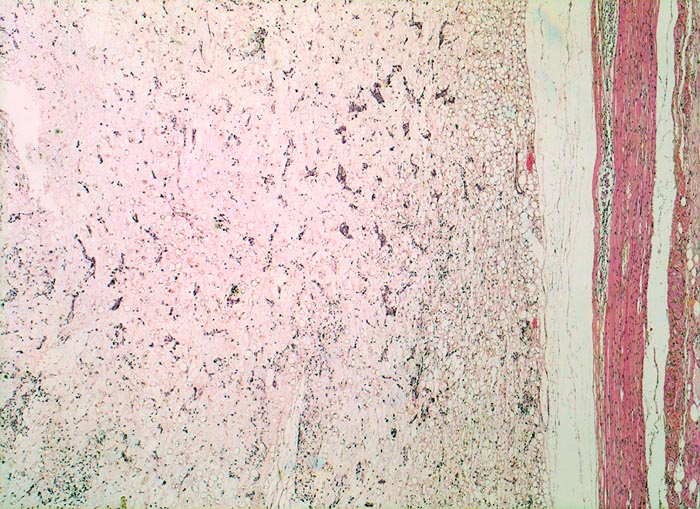

• Am rechten Rand des Präparates komprimierte Skelettmuskulatur.

• Links daran angrenzender scharf begrenzter Tumor mit reichlich myxoidem Stroma.

• Zahlreiche, überwiegend univakuoläre Lipoblasten. Zellkern durch die Lipidvakuole komprimiert und zur Seite verdrängt.

• Zahlreiche krähenfussartig verzweigte Kapillaren.

• Die rundzelligen Anteile erscheinen in der Übersicht aufgrund des Zellreichtums dunkler. Sie bestehen aus dicht gelagerten zytoplasmaarmen Tumorzellen mit vesikulären runden Kernen und einem prominenten Nukleolus.